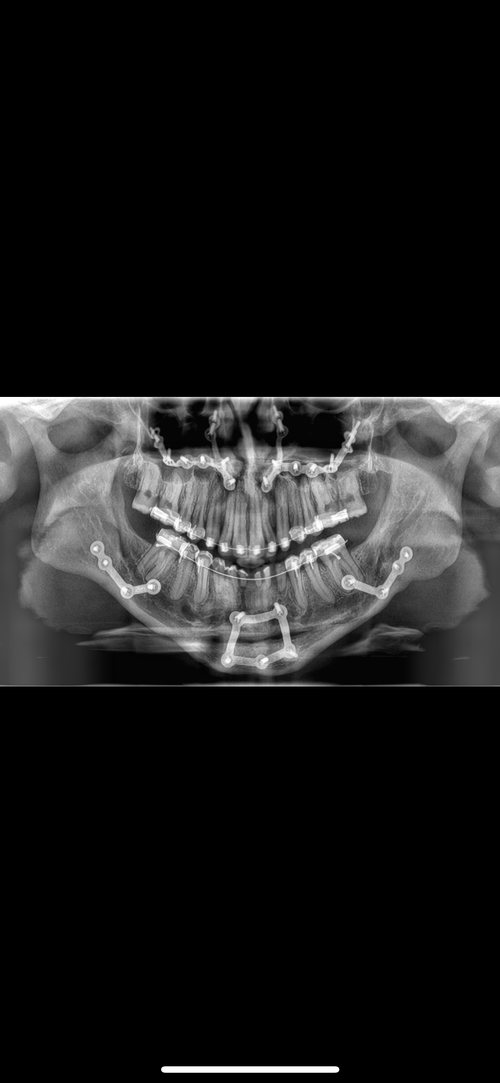

Hey guys long story short, I’m going ahead with jaw surgery revision + facial implants (low bone mass) first surgery was very conservative. I have a steep occlusion and jaw recession etc. If anyone with bimax knowledge could comment or help a niggah out I’d appreciate it ty faggets